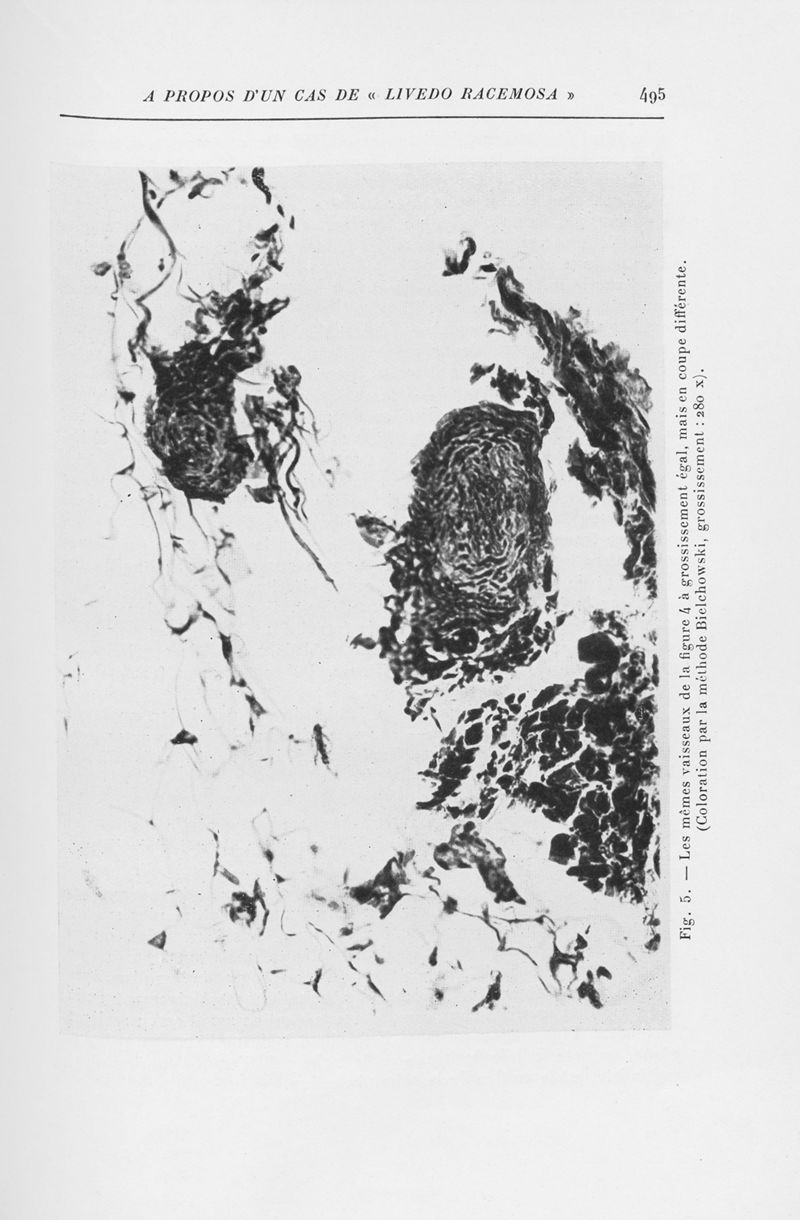

Annales de dermatologie et de syphiligraphie

7ème série, tome V. - Paris : Masson, 1934.